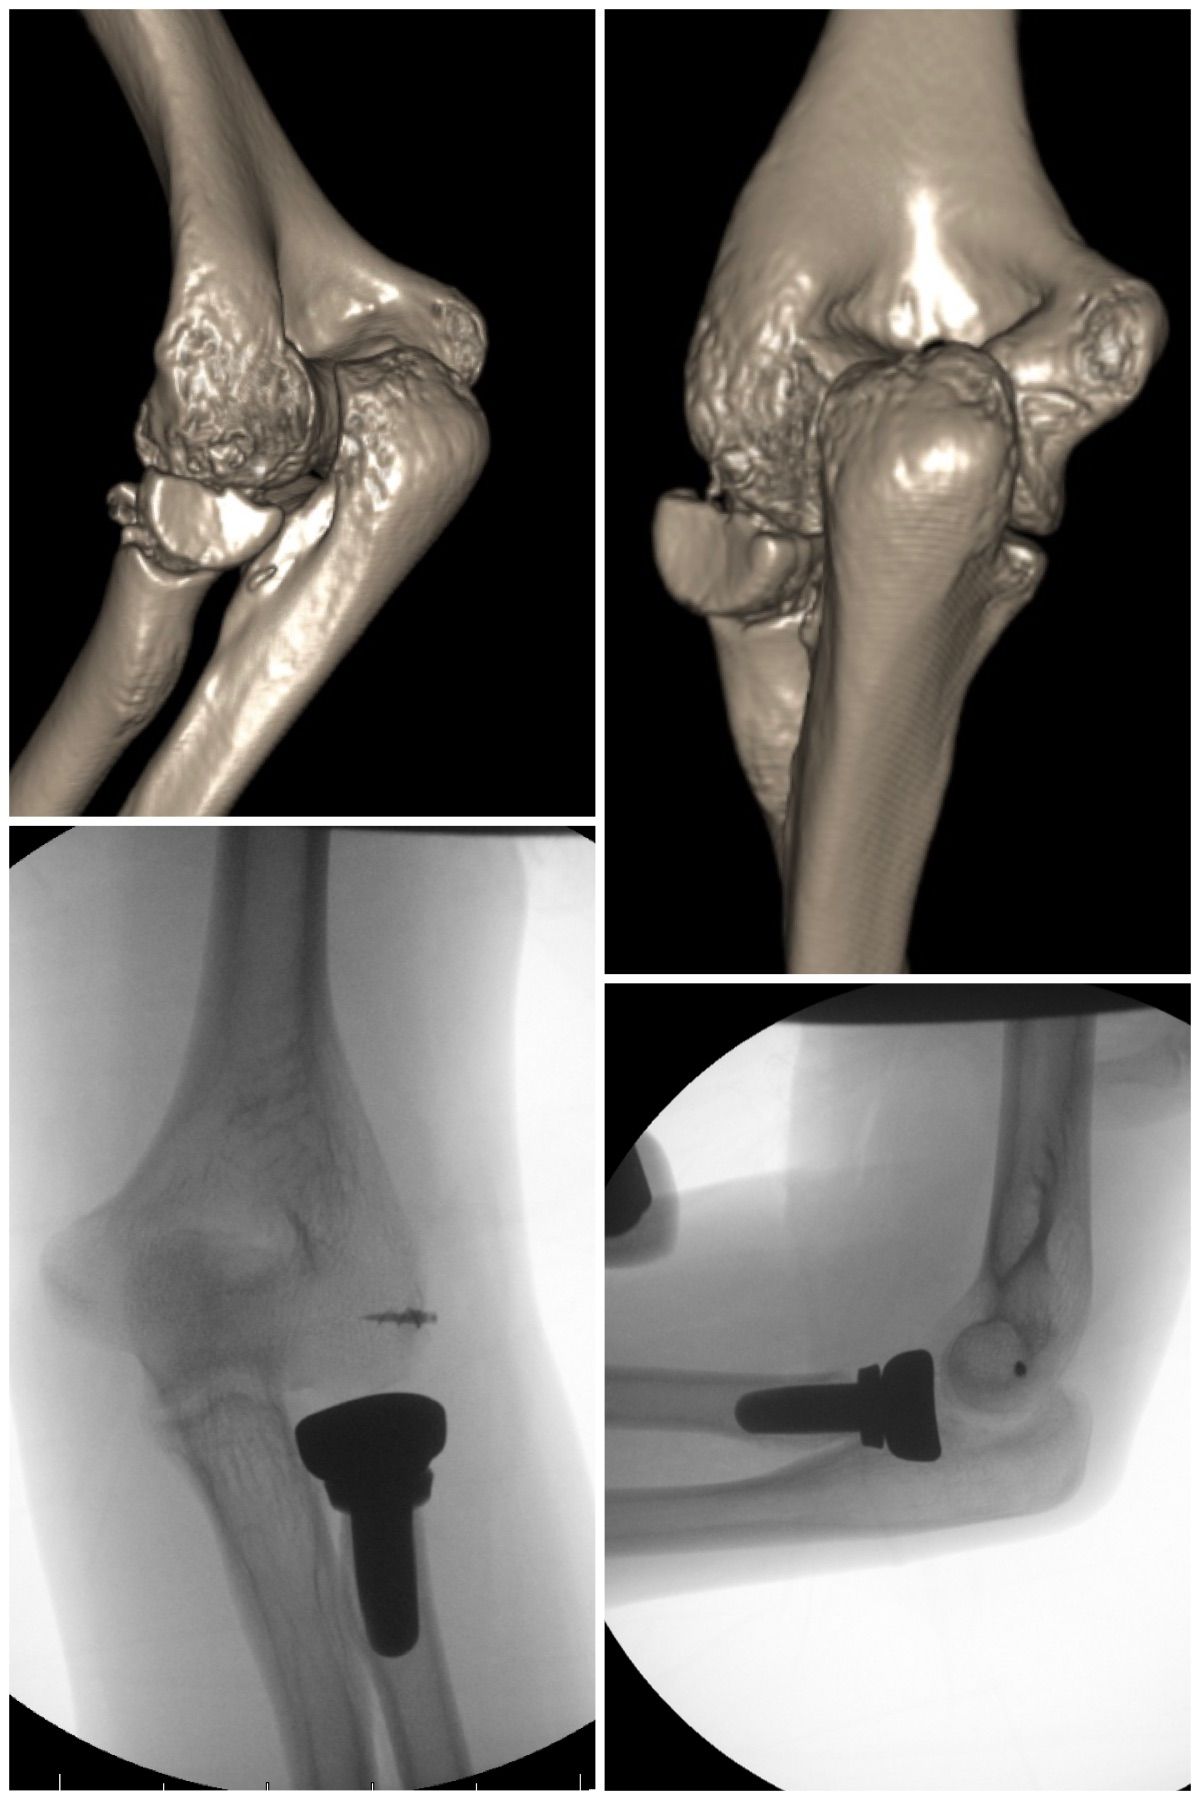

Se especializa en Síndrome del Manguito Rotador, Artroscopía de Hombro, Luxación de Hombro, Epicondilitis Lateral (Codo de Tenista), Fractura de Clavícula, Disyunción Acromioclavicular, Fracturas de Codo.

Conferencista. Tríada Terrible del Codo. II Jornadas de Traumatología. Hospital Universitario de Caracas (HUC). Caracas, Venezuela. 2015